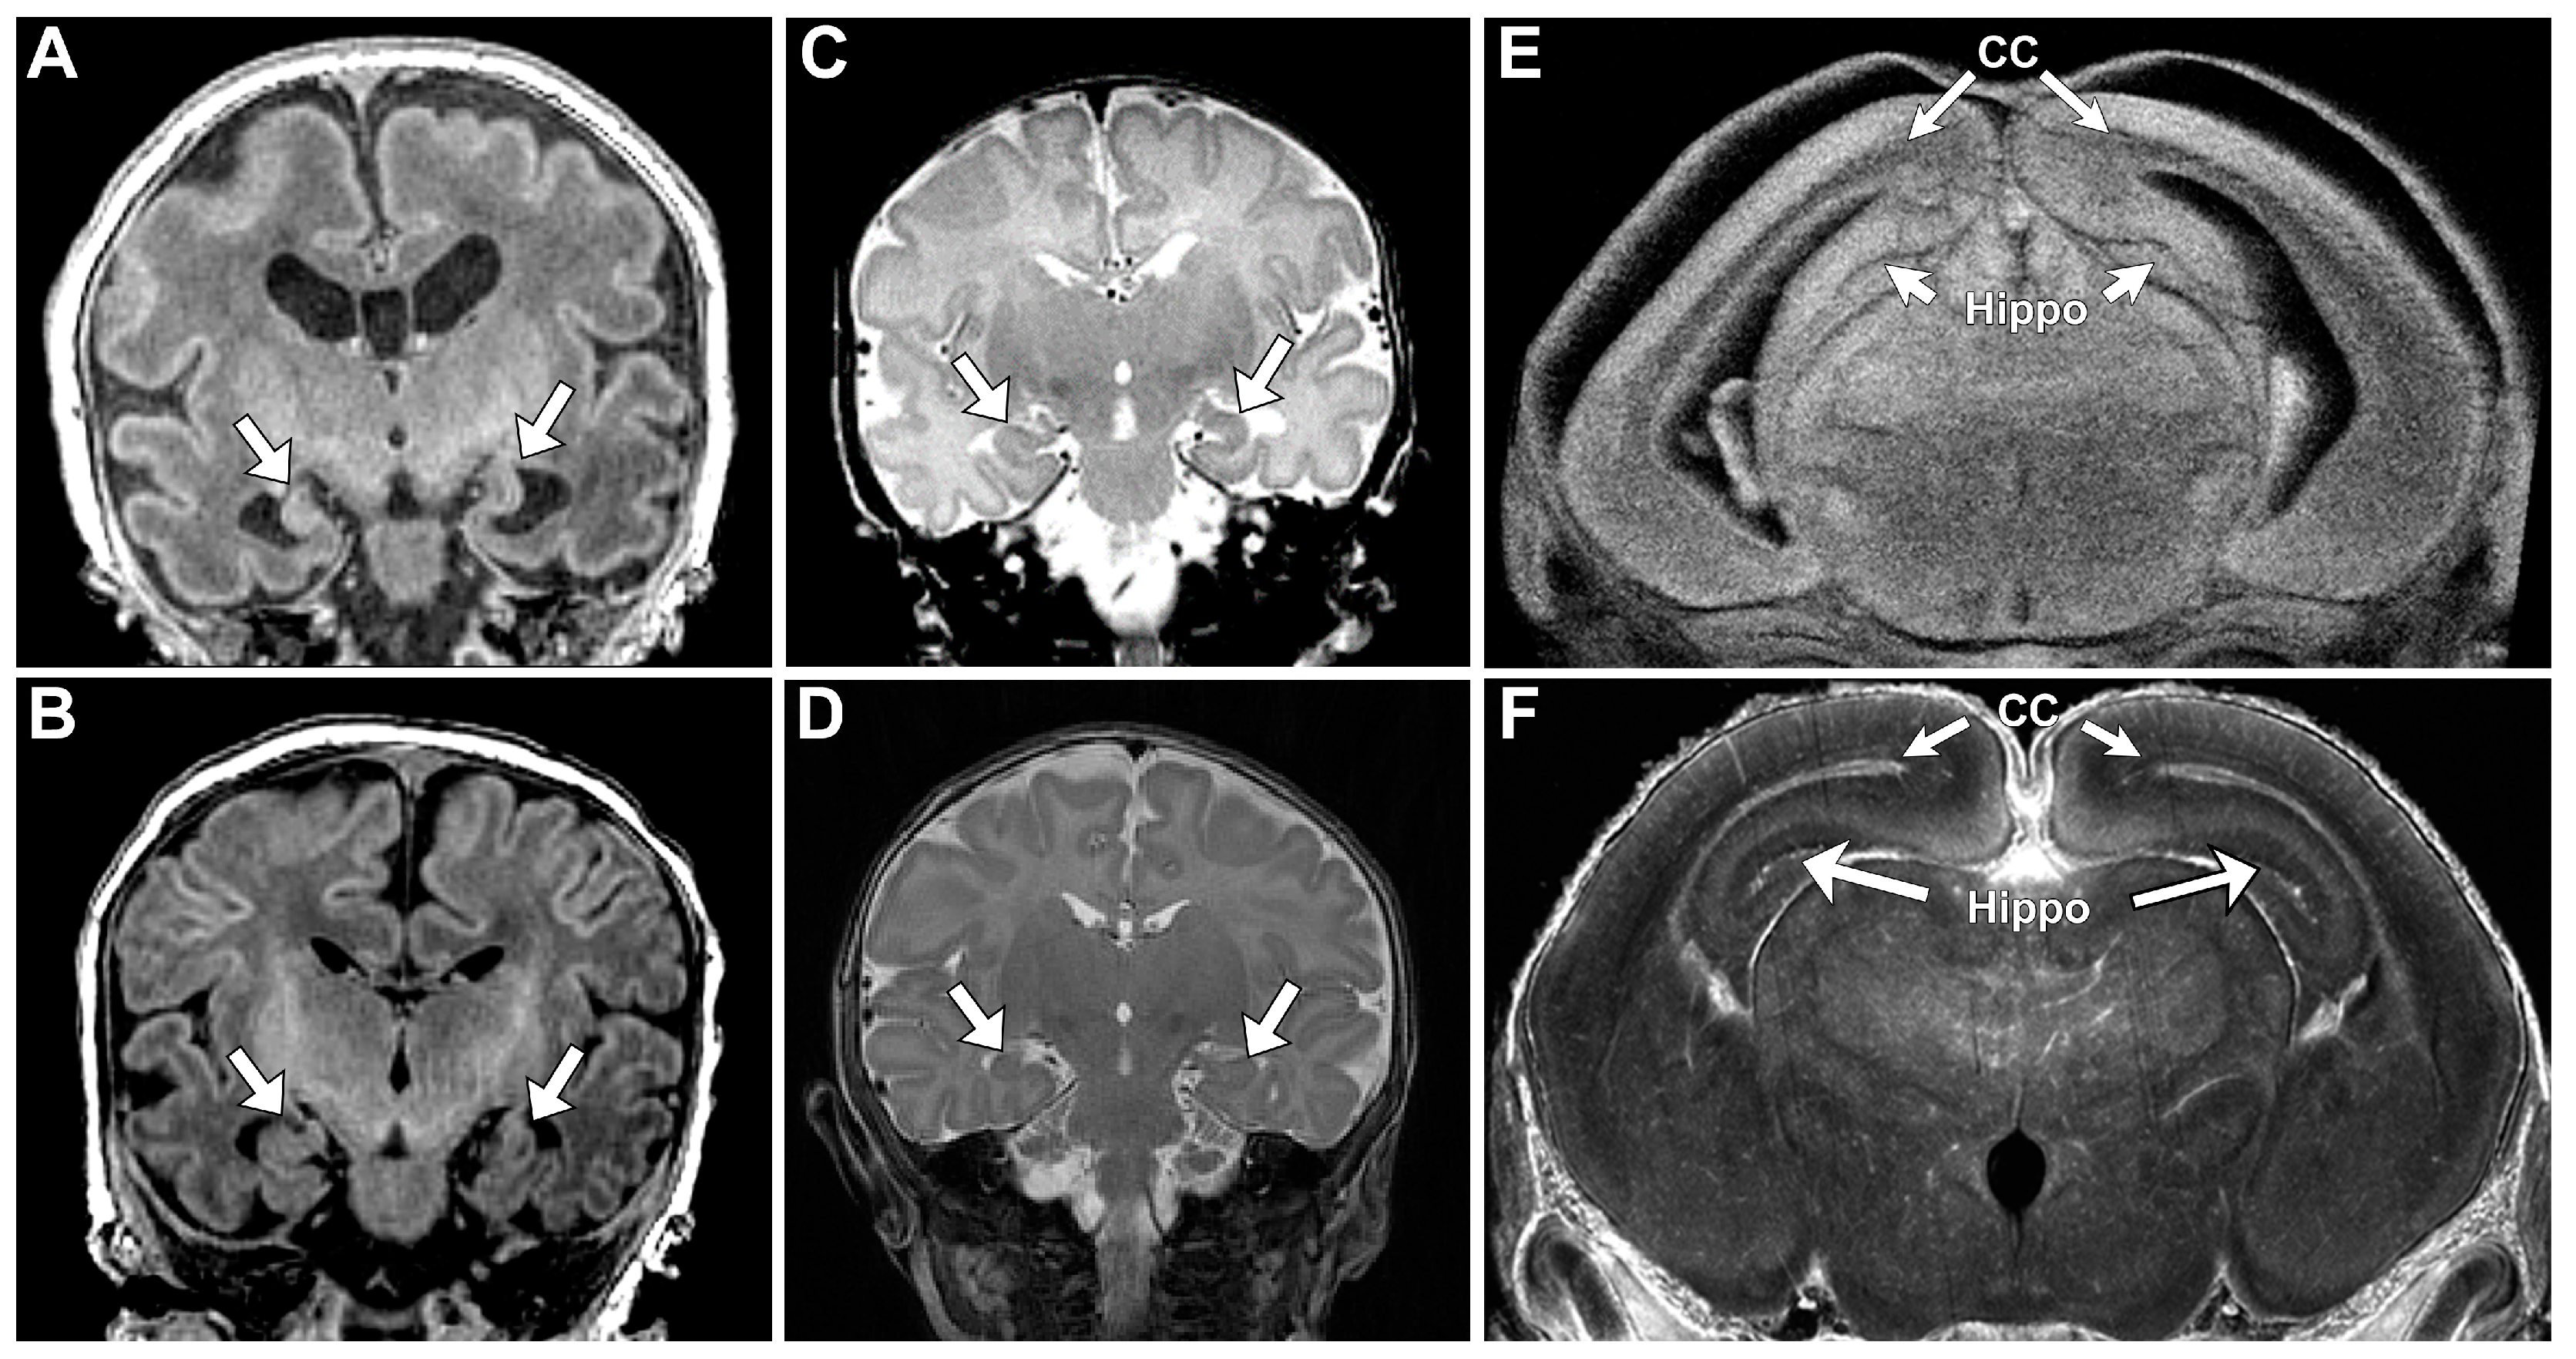

Lack of oral feeding before neonatal hospital discharge was associated with multiple morphological abnormalities of the components of the BDS including cerebellar hemispheres and vermis, hippocampus, bilateral olfactory bulbs and olfactory sulci, corpus callosum, increased supratentorial extra-axial fluid, as well as total increased BDS (Table 7). Hospital length of stay was associated with dysplasia of the cerebellar hemispheres and vermis, hippocampus, choroid plexus, brainstem, increased supratentorial axial fluid, and BDS (Table 7). A diagnosis of dysphasia was associated with dysplasia of the brain stem ((p = 0.001) Table 7). Gastrointestinal dysmotility, aspiration, gastroesophageal reflux, malrotation, and vocal cord paralysis demonstrated no significant associations with brain dysplasia (Table 7). Figure 2 panels A–D show some of the variations in hippocampal anatomy seen in the human population compared against that seen in the mouse in panels E and F. Figure 3 demonstrates olfactory bulb abnormalities in human infant CHD vs. control (A/C) and the mouse model (B/D). Figure 4 demonstrates cerebellar abnormalities in the human infant CHD vs. controls (A,B) and the mouse model (E,F).

An important component of our paralimbic-related subcortical BDS scoring system is the hippocampus. We found a consistent pattern of dysmaturation in the hippocampus, including severe forms of hippocampal aplasia or dysplasia in both mice and human subjects. Research has indicated that reductions in hippocampal volume has functional correlates in adolescents and adults, resulting in an increased rate of neurodevelopmental impairment [65,66]. Fontes et al. found that hippocampal shape and volumetric abnormalities found within CHD subjects can be predictive of impaired executive function. It is possible that the hippocampus is particularly vulnerable to early injury in CHD individuals as it is a brain region particularly susceptible to injury related to hypoxemia or hemodynamic instability. Latal et al. found that reductions in hippocampal volume correlated with reductions in total IQ, working memory, and verbal comprehension. Lastly, one study looking at maternal stress found that reductions in hippocampal volumes are present in utero, consistent with previous volumetric findings of CHD [67]. Wu et al. concluded that universal screening looking at maternal stress is important, as early identification of hippocampal abnormalities is imperative.

Another important component of our paralimbic-related subcortical scoring system was the cerebellum. Cerebellar dysfunction has been linked with adverse neurodevelopmental outcomes [68,69,70]. Stoodley found that cerebellar damage or malformation present in early stages of development to be more detrimental than when obtained in adulthood and theorized that injuries could affect cerebral–cerebellar circuits that are crucial to development and learning [69]. Zwicker et al. found that preterm infants with exposure to morphine in the neonatal period had decreased cerebellar volumes and worse neurodevelopmental outcomes [70]. Additionally, our group has previously shown that CHD children with reduced cerebellar volumes scored worse in tests for working memory, inhibitory control, and mental flexibility [71]. We also demonstrated that the superior surface of the cerebellum, primarily composed of the posterior lobe and the midline vermis, is an area particularly susceptible to alterations in morphology, indicating possible regions specifically affected by dysmaturation in CHD [23]. Previous literature in combination with our BDS findings show the importance of the cerebellum toward neurodevelopment and suggest that insults or injury affecting proper cerebellar development may impact neurodevelopmental outcomes. Figure 4 demonstrates some of the commonalities seen between the mouse and human cerebellum; of note are the abnormal number of cerebellar fissures and small size.